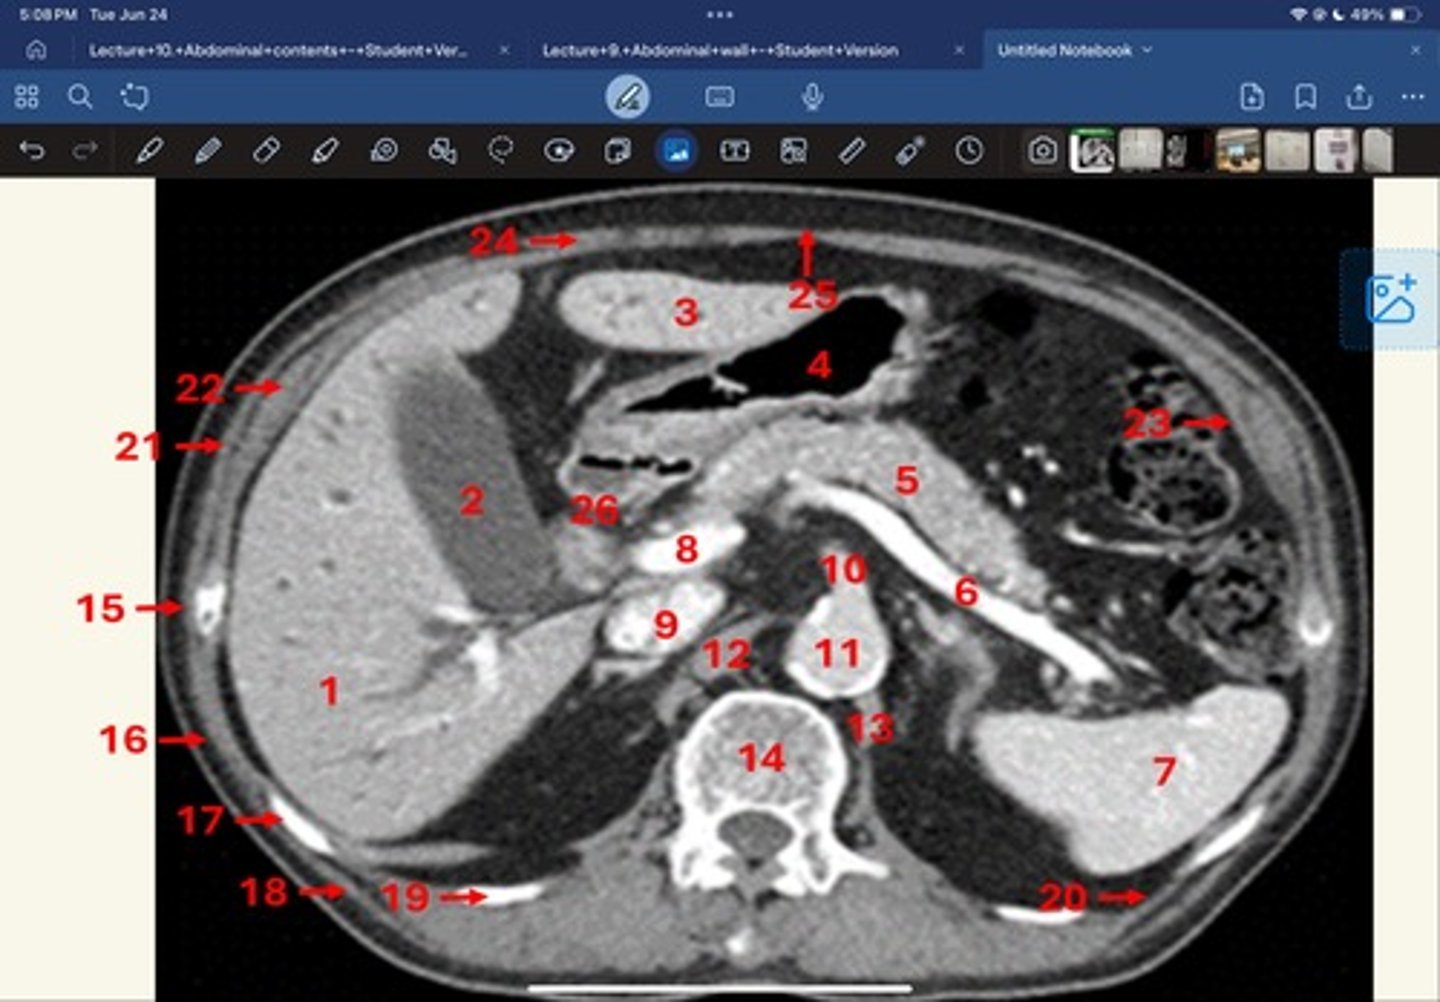

Right lobe of liver

What is 1

Gallbladder

What is 2

Left lobe of liver

What is 3

Stomach, pylorus

What is 4

Pancreas

What's 5

Splenic vein

What's 6

Spleen

What's 7

superior mesenteric vein

What's 8

Inferior vena cava

What's 9